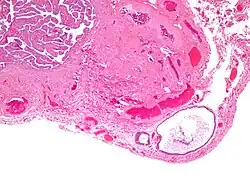

Walthard cell rest

- Cyst (may also be solid nest) of transitional type epithelium.

- Eosinophilic luminal secretions.

Walthard cell rests, sometimes called Walthard cell nests, are a benign cluster of epithelial cells most commonly found in the connective tissue of the fallopian tubes, but also seen in the mesovarium, mesosalpinx and ovarian hilus.

Appearance

They appear as white/yellow cysts or nodules that can reach a size of 2 millimeters. They typically have elliptical nuclei with a long groove (along the major axis) – so-called "coffee bean" nuclei.